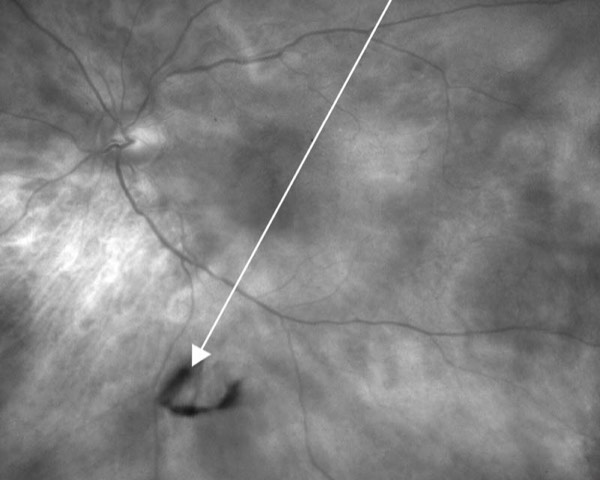

Der Glaskörper besteht aus einer klaren, gelartigen Substanz in der Hauptkammer des Auges zwischen der Linse und der Netzhaut. In jungen Jahren ist der Glaskörper vollkommen durchsichtig. Mit der Alterung des Auges degeneriert der Glaskörper und verliert dabei seine Form und verflüssigt sich teilweise. Dabei verdichten sich Kollagenfasern zu Knoten oder Strängen. Diese Gewebeklumpen sind die Ursache für Schatten auf der Netzhaut, die als Punkte, Fäden oder Spinnennetze erscheinen und als „Floater“ (deutsch: Schwebeteilchen) oder „Mouches volantes“ (deutsch: fliegende Mücken) bezeichnet werden. In vielen Fällen mit fortschreitender Degeneration kann sich der Glaskörper meist im Alter von 50 – 60 Jahren komplett von der Netzhaut ablösen. Dies ist nicht mit einer Netzhautablösung zu verwechseln! Diese hintere Glaskörperabhebung ist oft mit einem plötzlichen Anstieg der Floaterbeschwerden durch den sogenannten Weiss oder Martegiani Ring verbunden. Bei dieser Struktur handelt es sich um einen Ring im Glaskörpergerüst. Mit diesem Ring ist der Glaskörper am Sehnerven fixiert. Bei der oben beschriebenen Glaskörperschrumpfung löst sich dieser vom Sehnervenkopf und flottiert frei vor der zentralen Netzhaut. Insbesondere diese ist für viele Patienten extrem störend.